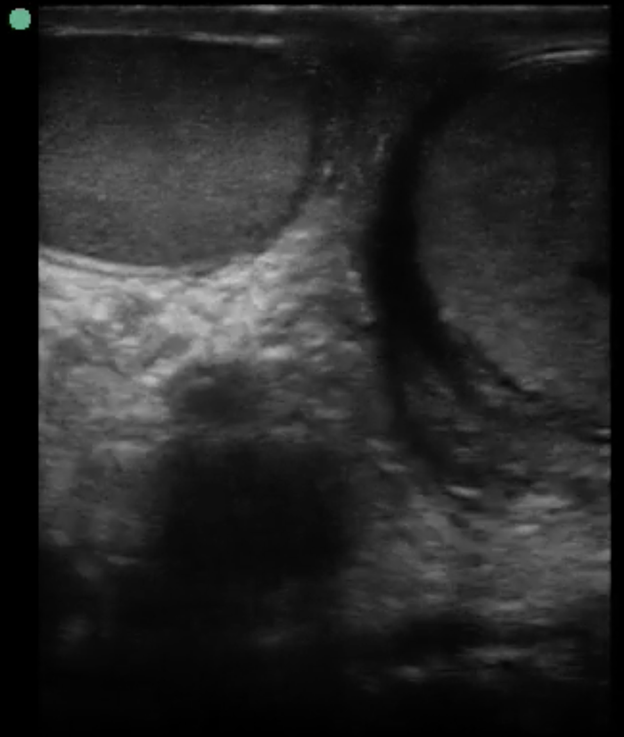

Image 2. Transverse “Buddy View” shows left predominant increased size of testis, heterogeneous echotexture, skin thickening, and mild hydrocele.

There are several signs of testicular torsion on scrotal ultrasound. Starting from the superior aspect, the spermatic cord can be seen with a whirlpool sign (knot-like) when compared to the unaffected side. This sign has high specificity with low sensitivity in Baud et al.,8 from 1998 and again demonstrated in McDowall’s meta-analysis in 2018.4 For now, the sign rules in testicular torsion but does not rule it out. Several other signs will favor the diagnosis, such as: spiral-like flow on color Doppler, an up-tracking epididymis as it is being dragged towards the inguinal canal, or an increased testicular size compared to a normal contralateral testis.

A hydrocele is common in acute torsion, as inflammatory edema builds in the surrounding tissue. However, it can be absent in chronic torsion. Scrotal skin edema and thickening may also be present.

The high-frequency probe (at least 7.5 MHz) should be used to evaluate the testicle. Ideally, the patient should be supine, knees bent with the hips externally rotated (frog leg position). The unaffected side should be scanned first in order to establish a baseline. Fully scan each testis, epididymis, and spermatic cord in both the longitudinal and transverse planes, starting medially and moving laterally. The portion of spermatic cord superior to the epididymis is where the whirlpool sign can be seen. It is imperative to obtain the view that includes both testes in order to evaluate for asymmetry, which is known as the “Buddy View.” Finally, color or power Doppler (the latter is more sensitive in low flow states but cannot differentiate direction) can evaluate for the presence or absence of blood flow to each testicle.11 The Doppler mode of choice should be power Doppler (which is up to 5 times more sensitive than color Doppler) to detect the “slow-moving” blood in the testes [10]. In case of ongoing torsion, the affected testicle will appear hypoechoic compared to the unaffected side as a result of edema and eventual necrosis.10